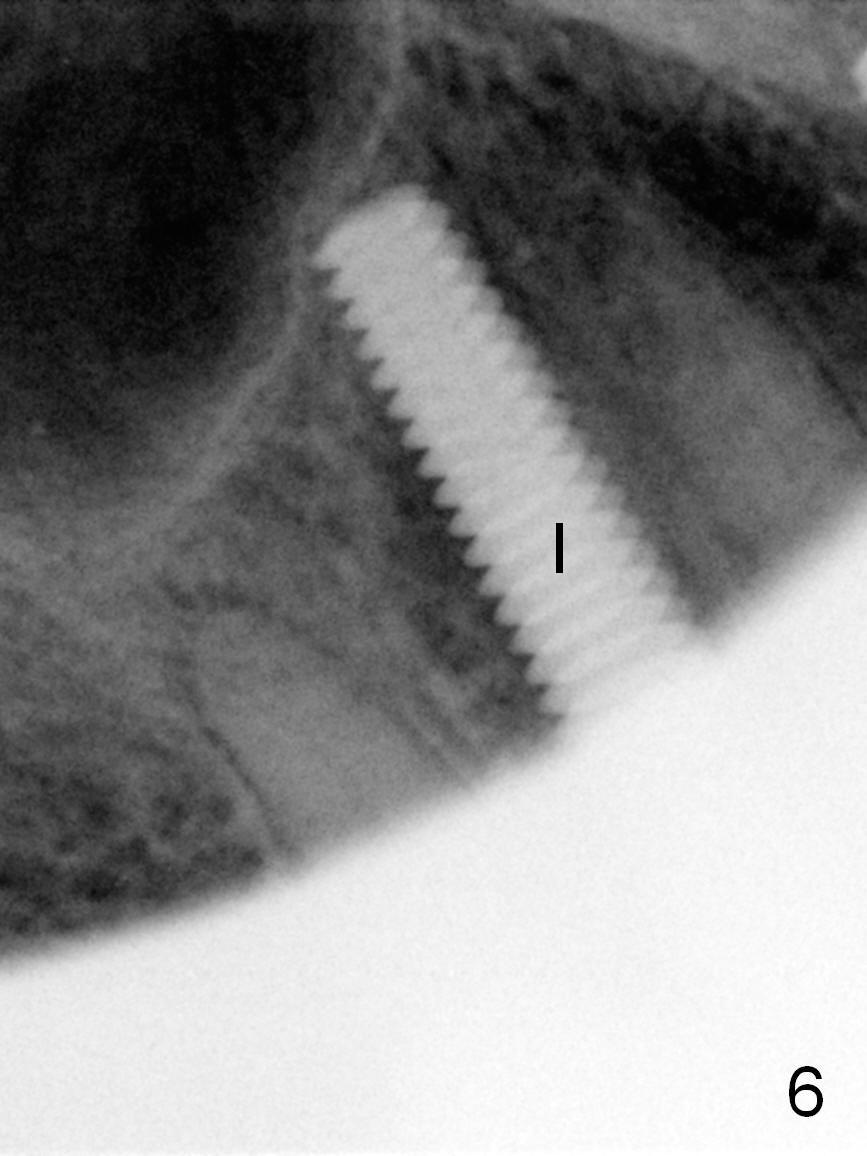

After long discussion, she agrees with extraction and immediate implant. After the extraction, granulation tissue is removed. There is buccal apical fenestration. The socket is treated with Metronidazole. The socket depth is 17 mm, while osteotomy depth is 20 mm (Fig.4). A 4x20 mm tissue-level implant is placed with primary stability (Fig.5,6 I). A short abutment (A) is placed immediately for an immediate provisional. The buccal gap is filled with Osteogen plug. There is no crestal bone loss 3 months postop (Fig.7). The provisional stays in place with occlusal perforation. The gingiva is healthy 5.5 months post cementation (Fig.8).